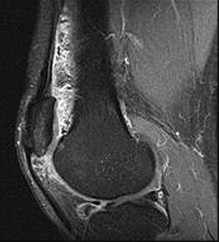

Figures 7a through 7d are the radiograph, MR images, and biopsy specimen of a 35-year-old man who has a painful, slowly enlarging knee mass. Which chromosomal translocation is characteristic of this pathology?

Synovial sarcoma is a soft-tissue sarcoma that usually occurs in young adults. Synovial sarcoma often causes pain, unlike most soft-tissue sarcomas, which generally do not cause pain. Imaging characteristics include soft-tissue calcifications on plain radiographs and a heterogeneous mass that is generally isointense to muscle on T1-weighted images and hyperintense to muscle on T2-weighted images. There are biphasic and monophasic types of synovial sarcoma. The biphasic

type, which is depicted here, has both spindle cell and epithelial components and will stain for both vimentin and cytokeratin. More than 90% of patients with synovial sarcoma have a characteristic genetic translocation of t(X;18), which results in the fusion protein SS18-SSX. This translocation can be stained for use of florescence in situ hybridization technology. t(11;12) is seen in Ewing sarcoma. T(9;22) is seen in extraskeletal myxoid chondrosarcoma. t(12;16) is seen in myxoid liposarcoma.